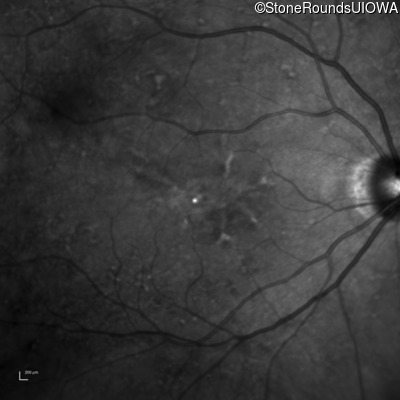

Infrared Fundus Photograph - Right - 20/20

Exemplar